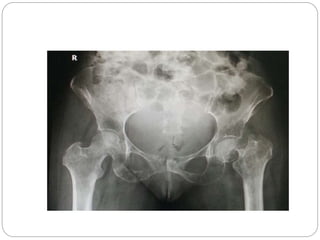

This document discusses 8 oncology cases. Case 1 involves a 40-year old female with right knee pain. Case 2 is a 28-year old male with a left subtrochantric fracture from a MVA who is now experiencing increasing left knee pain and swelling. Biopsy results showed high-grade osteosarcoma. Case 3 is a 30-year old female with breast cancer and bone metastases causing bilateral hip pain.